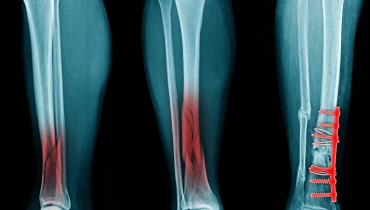

Остеосинтез голени – это распространенное в травматологии и ортопедии хирургическое вмешательство, суть которого заключается в восстановлении целостности большеберцовой и малоберцовой костей при травматических их повреждениях. Врач сопоставляет разрушенные костные отломки. Затем осуществляет проведение фиксации в правильном положении с помощью металлических конструкций. Тем самым добивается консолидации перелома с сохранением анатомически правильного расположения. В окончании лечения пациент полностью возвращает себе функцию конечности. Может в прежнем объеме нагружать ногу, ходить или заниматься спортом, не опасаясь дискомфорта, осложнений.

Интрамедуллярный остеосинтез голени проводится с использованием особых стержней и штифтов. Травматолог вводит изделие в кость по ходу костномозгового канала. Собирает фрагменты, как будто насаживает бусины на проволоку. Целостность кости восстанавливается. На всем протяжении формируются мозоли.

Экстрамедуллярный вариант лечения — это остеосинтез голени пластиной. Металлическая конструкция вводится уже не внутрь кости, а устанавливается кнаружи от нее, поверх раздробленных частиц. Фиксирует травматолог последнюю винтами с блокированием.

Чрескостный способ соединения отломков — это остеосинтез голени аппаратом Илизарова. Врач продлевает спицы перпендикулярно фрагментам разрушенной кости. Закрепляет их с внешней стороны в специальной металлической дуге. Фиксирует винтами. По мере стабилизации костных отломков травматолог может расслаблять винты, уменьшать натяжение.

Комбинированный вариант сочетает в себе остеосинтез голени винтом, спицами, штифтами и другими металлическими конструкциями. Когда только одним способом добиться результата не получается, врач использует сразу несколько методик восстановления целостности большеберцовой и малоберцовой костей.